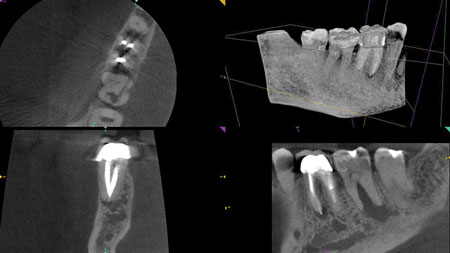

As an endodontist, cone-beam computed tomography (CBCT) has become an invaluable part of my practice. The CS 9000 3D from Carestream Dental lets me view the finite detail of root morphology in stunning 3-D detail. It is technology that gives me an edge. General practitioners know that my system allows me to diagnose and treat patients with more success than conventional clinical tests or 2-D radiographs, which would require 33% bone destruction to reveal even a fraction of what I'm able to see with CBCT.1 Over the years, I've used my CBCT system as a way to gain and build relationships with general practitioners, and establish the kind of referral base that happily sends me patients from across the state.

Radiolucency seen on the first molar, and the second molar demonstrates major bone loss in furcation due to a fractured root. The axial view depicts a resorptive defect along the actual fracture line.

The buccal and palatal plates of bone are intact here, but there is tremendous infection in the furcation.

CBCT shows a missed MB2 on the last tooth, the second molar.

The CBCT scan reveals palatal root resorption.